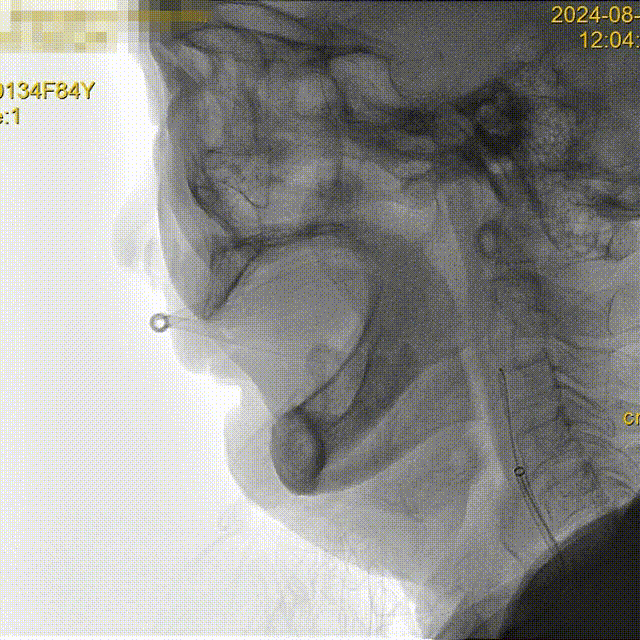

泥鳅塑型,携带125cm长SIM2进入右颈总。

什么叫桡鞘【例久弥新】寻道于桡——瑞康通5.5F IntroSky X导管鞘经桡动脉行右侧大脑中动脉取栓一例_https://www.jmylbn.com_新闻资讯_第11张

5.5F IntroSky X导管鞘顺利绕过迂曲段进入颈总动脉。

通路尽量高到位,同时注意避免血管痉挛、血流阻断。